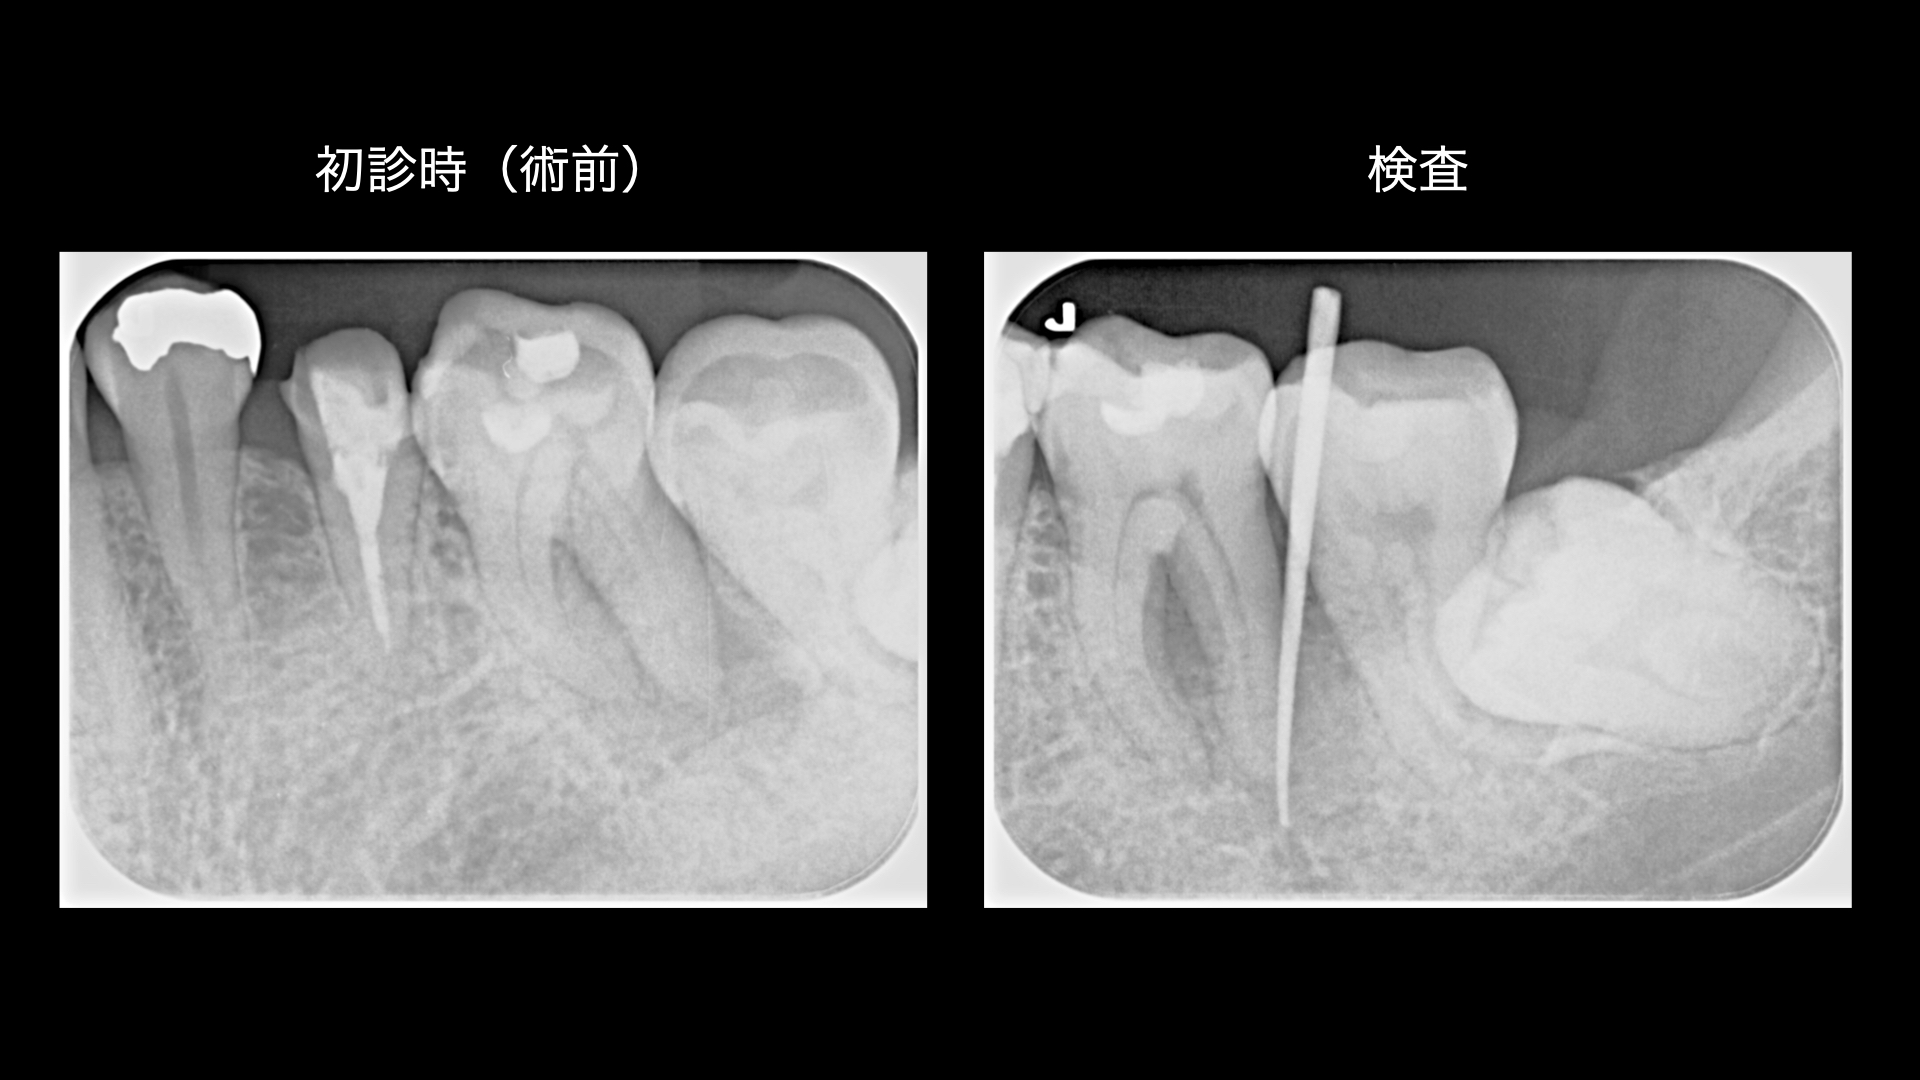

噛んだ際の違和感や、歯ぐきから膿が出る症状を主訴に来院されました。検査の結果、歯の根の先に大きな根尖病変が認められ、周囲の骨が広範囲に吸収されている状態でした。また、歯根の湾曲が30度を超えており、通常の根管治療では十分な治療精度を確保することが難しい高難易度のケースでした。

治療(根管充填確認時)